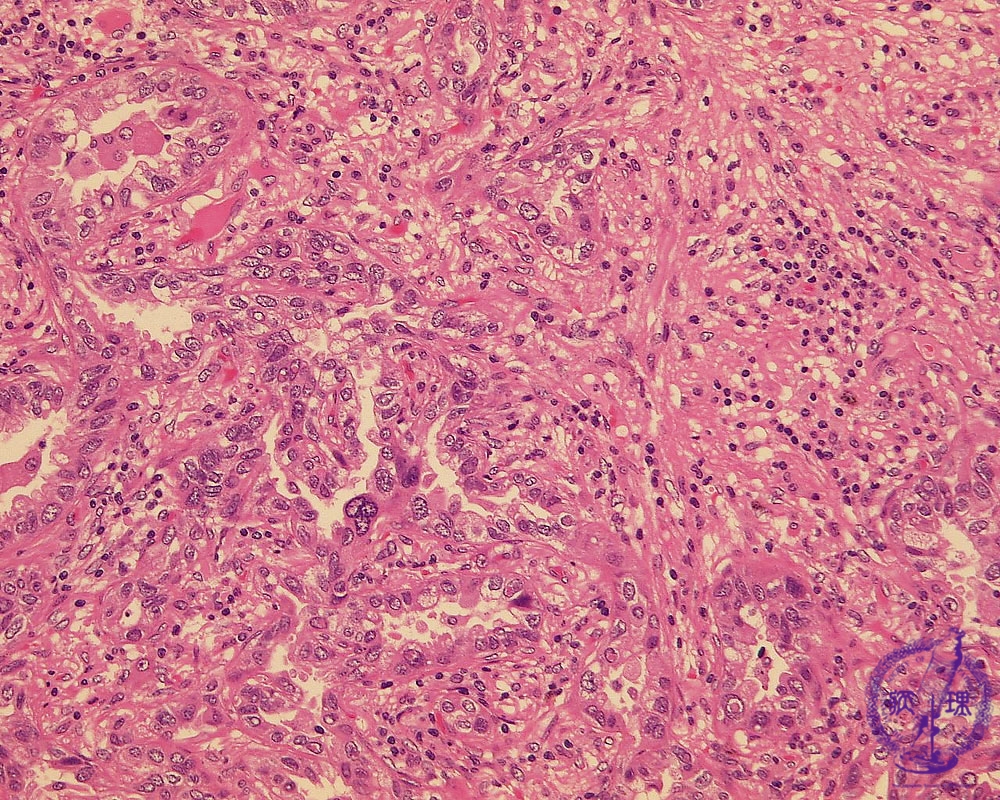

非小細胞肺癌(腺癌)ミクロ像(HE強拡大)

ミクロ像(HE強拡大):腫瘍中心部、浸潤癌の部分では腫瘍細胞は不規則な腺腔を形成しながら浸潤性に増殖している。複雑に入り組んだ間質(星印)にはリンパ球を中心とした炎症細胞の浸潤が見られる。